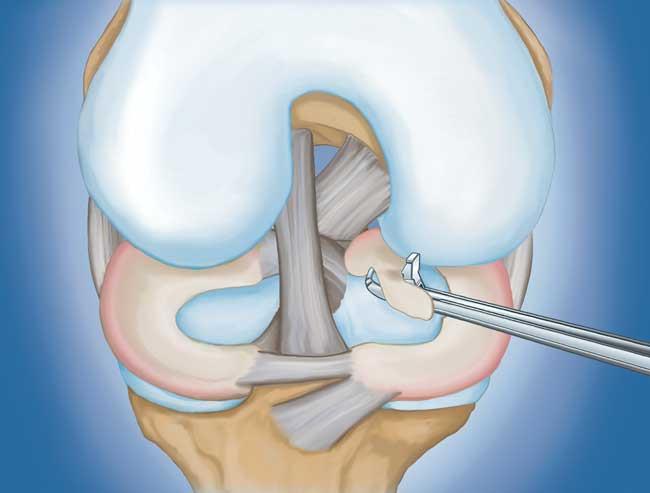

• 部分半月板切除術(shù)。  在這個(gè)過(guò)程中,受損的半月板組織被修剪掉。該程序通常允許在手術(shù)后立即負(fù)重和全方位運(yùn)動(dòng)。

部分半月板切除術(shù)特寫(xiě)